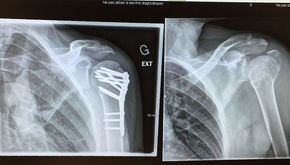

In February 2016 I was diagnosed with locally advanced stage II breast cancer. As we gathered ourselves to meet that challenge, my wife fell on an icy driveway, shattering her shoulder. She required major surgery on the same day as I began chemotherapy. Together - two abreast - we navigated a year of treatment and recovery. This blog collects my writing through our experience. As of June 2024, we are both recovered and thriving - grateful for each new day and the people and resources in our lives.